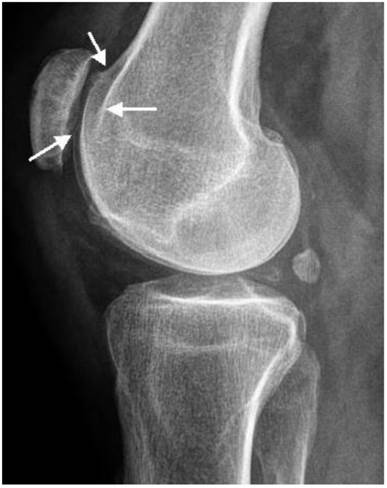

Patellar instability has been referred to patello-trochlear dysplasia (anterior knee pain associated with patellar instability) in connection with joint hypermobility and epiphyseal dysplasia has been encountered in all patients. Lateral knee radiograph showed trochlear dysplasia, including the crossing sign, supratrochlear spur, and double contour (a hypoplastic medial facet) associated with patellar dysplasia and patellar maltracking in a 9-year-old patient (fig 7). The skyline view in female patient aged 17-years-old showed mal- tracking of the patella with trochlear dysplasia associated with severe hyperpression of the patello- femoral joint, with subchondral degenerative changes (this is a common feature in patients with patellar instability in connection with patello-trochlear dysplasia associated with profound femoral notching), also, this is compatible with osteoarthritis of the patella-femoral joint (fig 8).

Fig 7

Lateral knee radiograph showed trochlear dysplasia, including the crossing sign, supratrochlear spur, and double contour (a hypoplastic medial facet) associated with patellar dysplasia and patellar maltracking in a 9-year-old-patient.